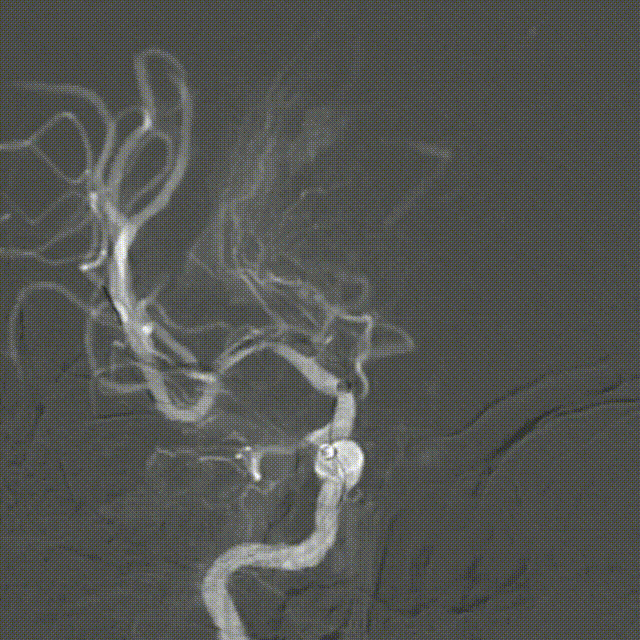

再次释放Syphonet®取栓支架 5*35mm,造影显示:支架释放效应阳性。

M1局部重度狭窄。

SacSpeed®球囊扩张导管 2.0*9mm球囊到位过程。

SacSpeed®球囊扩张导管 2.0*9mm球囊到位造影:血管再闭塞。

SacSpeed®球囊扩张导管缓慢扩张过程中见明显腰线。

球扩后造影:狭窄明显改善,前向血流明显好转,未见血栓征象,球囊部分回收支架,撤出。